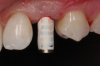

(50.) An opaqued titanium abutment was placed on the implant, and the natural tooth shell was then bonded to the abutment with flowable composite in the incisal half.

Figure 50

(51.) Palatal view of the partially completed natural tooth provisional restoration after it was removed from the mouth.

Figure 51